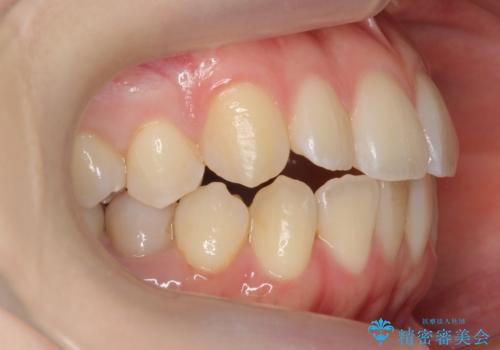

下の八重歯 歯を抜かずに インビザライン治療

- 歯並びのがたつきを主訴に来院。

抜歯してワイヤー矯正という選択肢も提案しましたが、マウスピース矯正で、歯を抜かずに並べてほしいとのことでした。

スペースを確保するために、歯をわずかに削る処置、奥歯を後ろに下げる処置(インプラント矯正)を行っています。

途中患者様のご都合で治療を中断していたため、長くかかっていますが、実質2年程度で終わる内容でした。